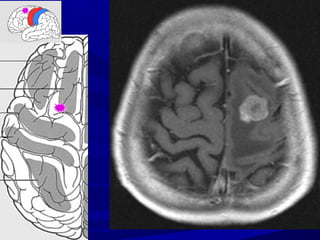

DI CAÊNDI CAÊN

NAÕONAÕO

NMN NAÕONMN NAÕO